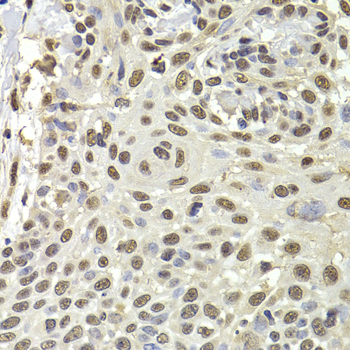

Immunohistochemistry - PUF60 Polyclonal Antibody

Immunohistochemistry of paraffin-embedded human well-differentiated squamous skin carcinoma using PUF60 antibody at dilution of 1:100 (40x lens).